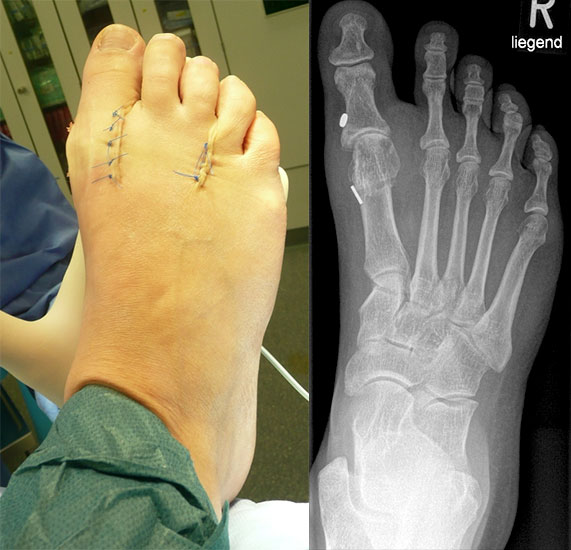

Gute Ergebnisse werden in diesem Fall durch die Arthrodese des MTP-1-Gelenkes erzielt. Bei älteren Patienten kann zum Erhalt der Beweglichkeit eine Keller-Brandes-Prozedur sinnvoll 2327, (Wirth, 2002)

Arthrodese MTP I und weichteilige Rezentrierung MTP II und III (eigenes Bildmaterial)

Abbildung 18

Eine alleinige Implantation einer Prothese oder eines Spacers im MTP-Gelenk bringt bei fehlender Ausrichtung der Zugrichtung der Muskulatur des 1. Strahles keine befriedigenden Ergebnisse.